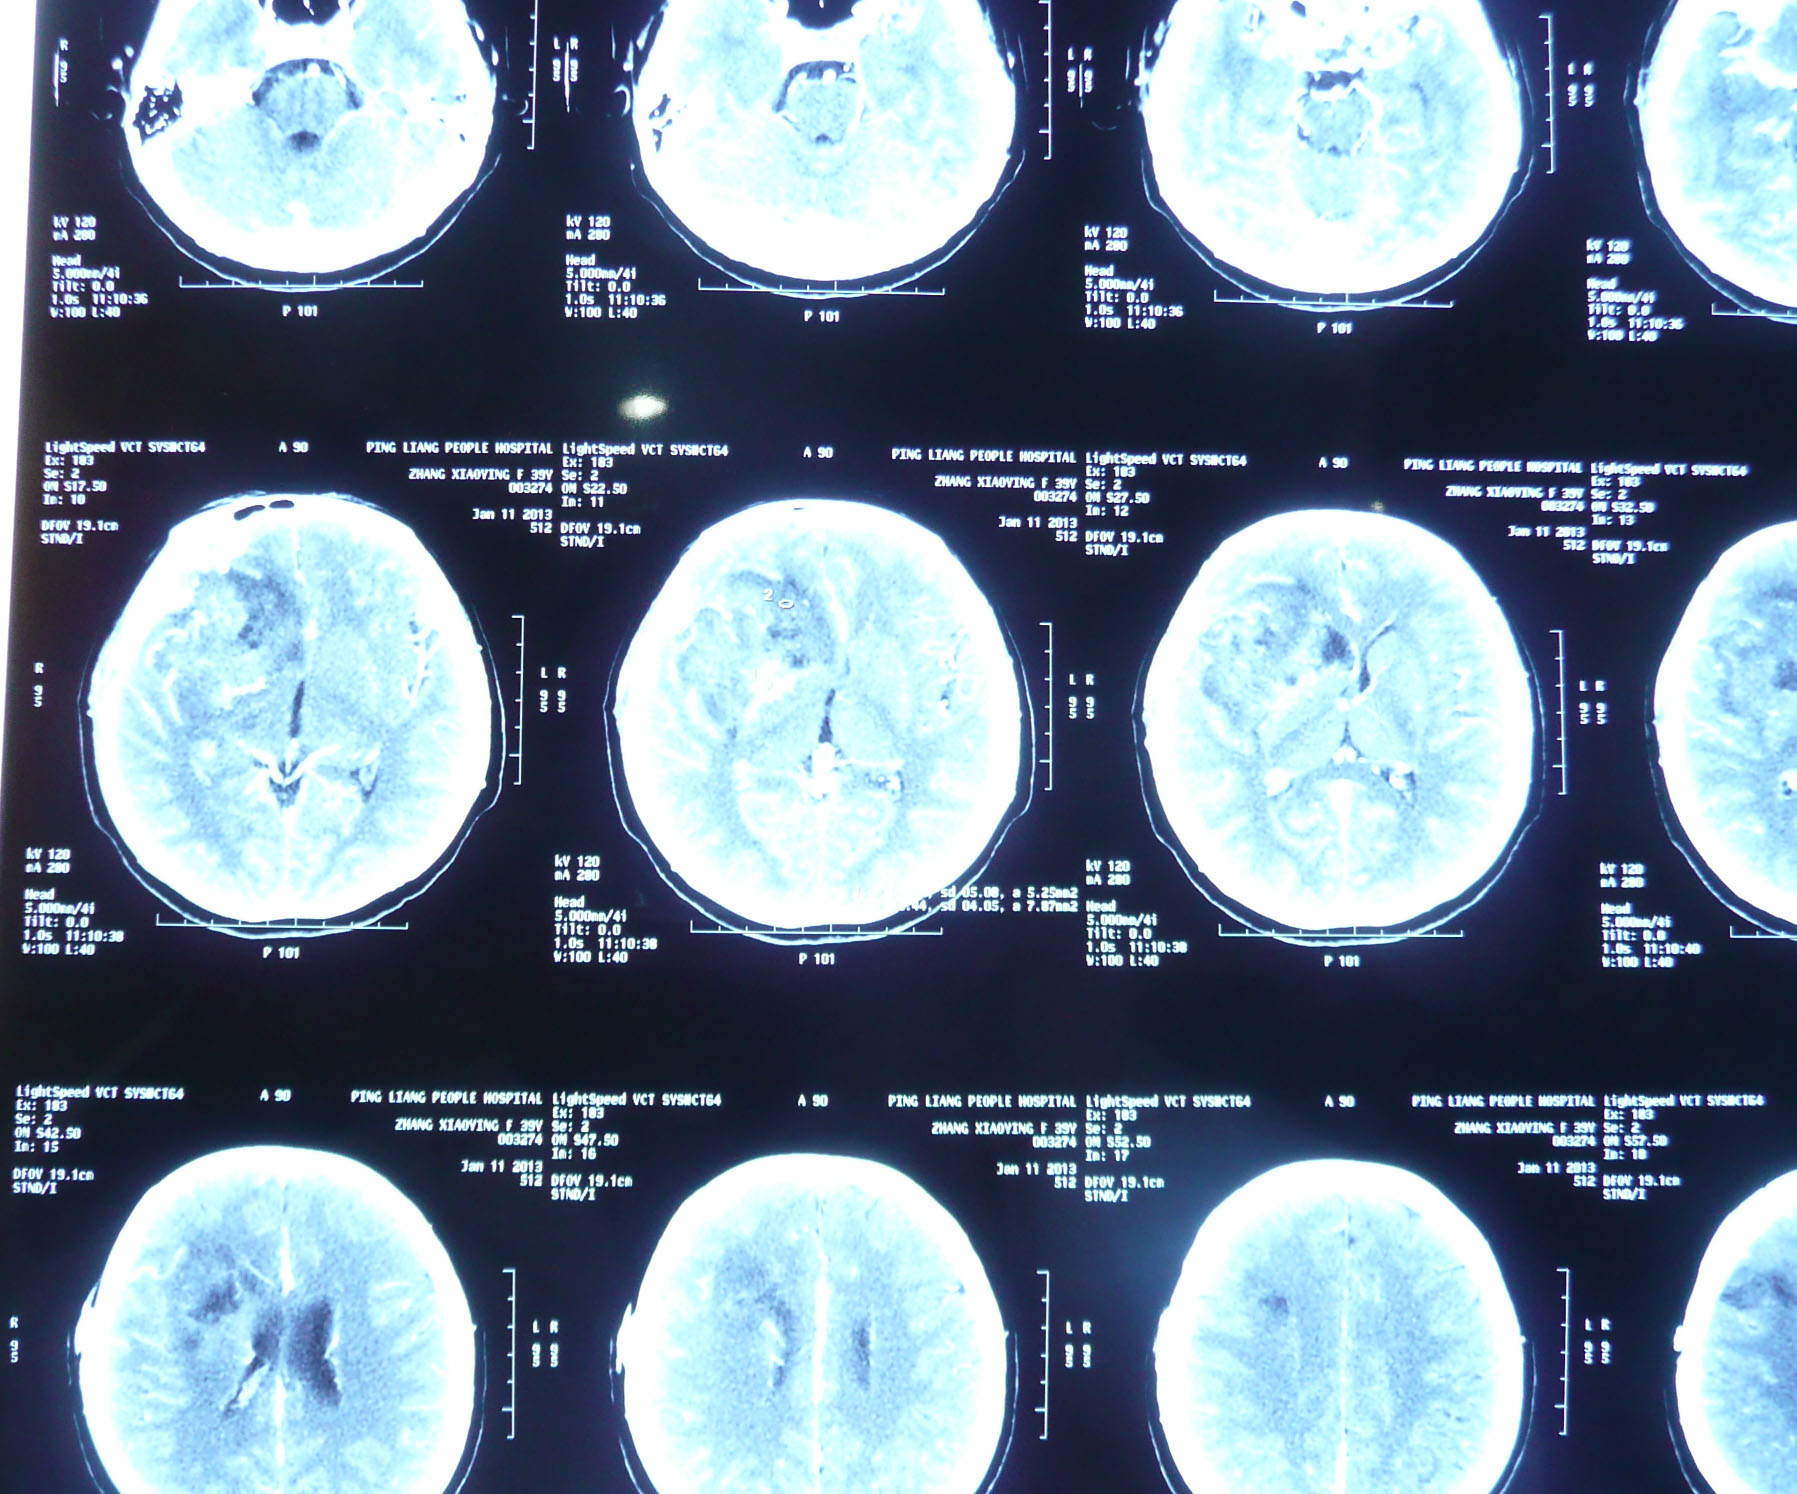

左侧小脑脑膜瘤 68岁女性,头痛伴行走不稳一月余入院